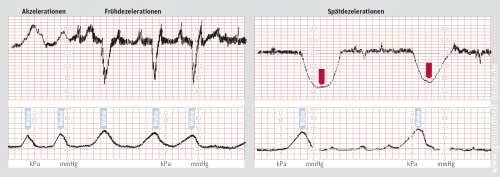

Die elektronische Überwachung der Geburts durch die Kardiotokografie, dem CTG also, gehört zum Pflichtprogramm bei der Klinikgeburt. Das CTG zeigt zum einen die Regelmäßigkeit und die Kraftentwicklung der Wehen (untere Kurven), und zum anderen, wie das kindliche Herz auf die Wehen reagiert (obere Kurven). Verkraftet der kindliche Kreislauf die Unterbrechung der Sauerstoffzufuhr während der Wehen gut, so steigt die kindliche Herzfrequenz bei jeder Wehe im Rahmen einer normalen Stressreaktion entweder an (Akzeleration, im linken Bild links) oder sinkt nur wenige Momente ab (Frühdezeleration, im linken Bild rechts). Gefährlich und Zeichen eines kindlichen Sauerstoffmangels ist, wenn das kindliche Herz verspätet und dafür gleich über mehrere Minuten hinweg langsamer schlägt (Spätdezeleration, rechtes Bild). Zeigt das CTG ein gesundes Wehenmuster, so wird es alle zwei Stunden für etwa 30 Minuten wiederholt. Zeigt es jedoch Spätdezelerationen oder eine ungenügende Wehentätigkeit, oder ist das Kind aus anderen Gründen gefährdet, bleibt das CTG kontinuierlich während der gesamten Eröffnungsphase angelegt.